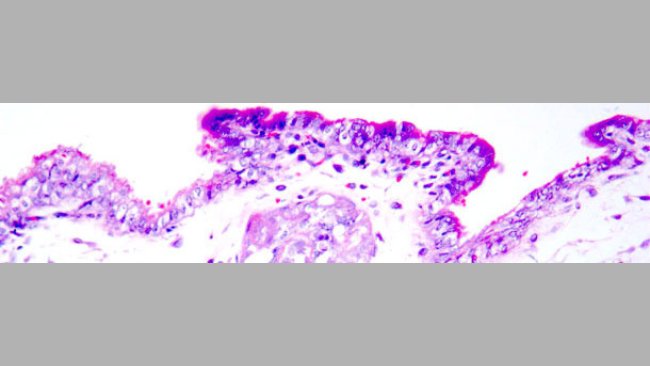

Descrição fotográfica das lesões mais significativas dos suínos